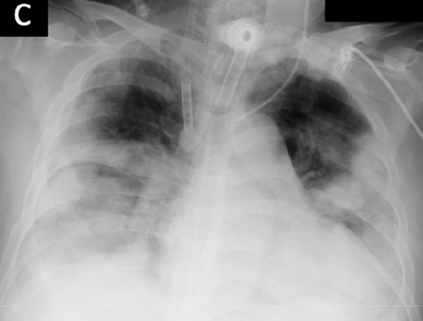

Across the world's coronavirus disease 2019 (COVID-19) hot spots, the need to streamline patient diagnosis and management has become more pressing than ever. As one of the main imaging tools, chest X-rays (CXRs) are common, fast, non-invasive, relatively cheap, and potentially bedside to monitor the progression of the disease. This paper describes the first public COVID-19 image data collection as well as a preliminary exploration of possible use cases for the data. This dataset currently contains hundreds of frontal view X-rays and is the largest public resource for COVID-19 image and prognostic data, making it a necessary resource to develop and evaluate tools to aid in the treatment of COVID-19. It was manually aggregated from publication figures as well as various web based repositories into a machine learning (ML) friendly format with accompanying dataloader code. We collected frontal and lateral view imagery and metadata such as the time since first symptoms, intensive care unit (ICU) status, survival status, intubation status, or hospital location. We present multiple possible use cases for the data such as predicting the need for the ICU, predicting patient survival, and understanding a patient's trajectory during treatment. Data can be accessed here: https://github.com/ieee8023/covid-chestxray-dataset